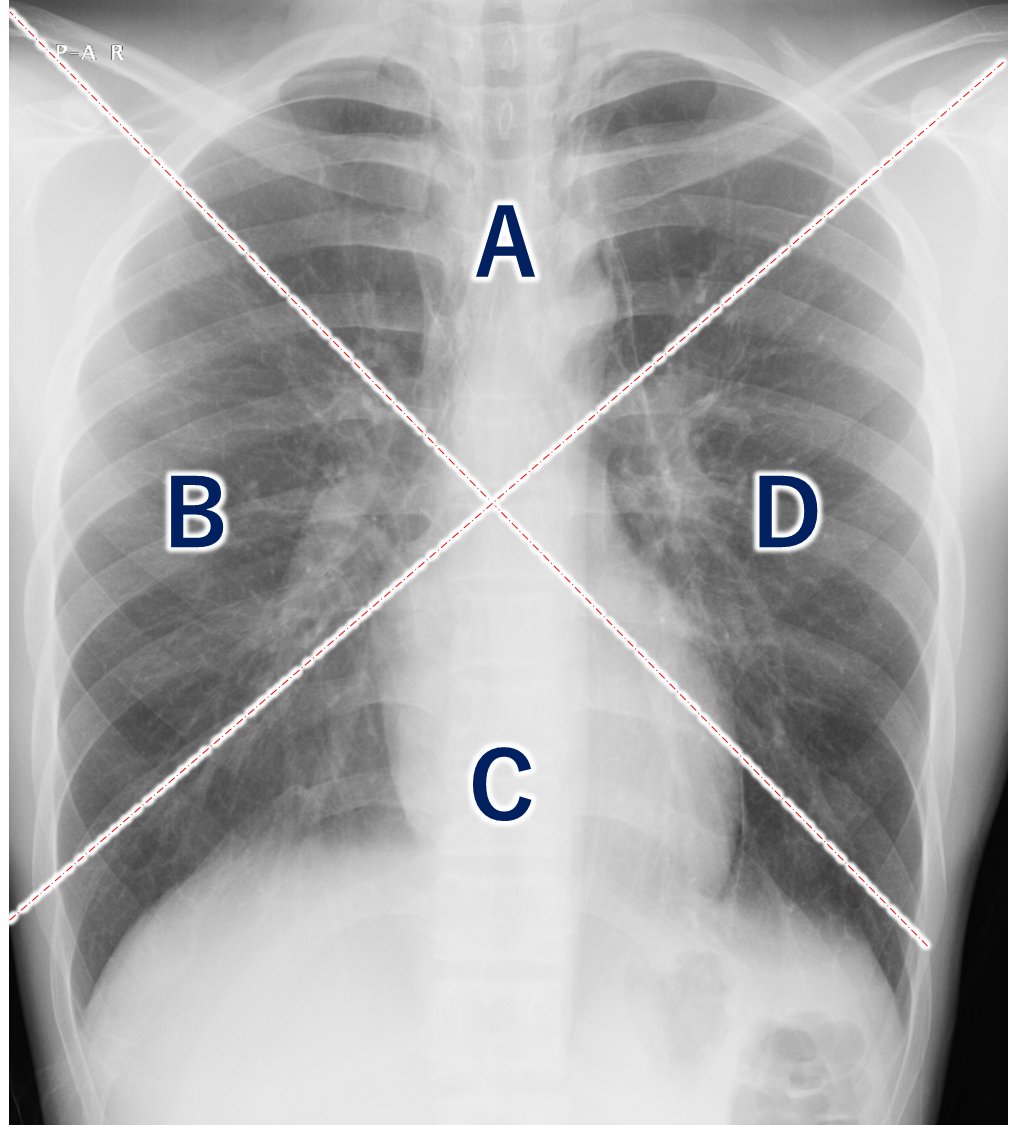

さてここで読影問題です。

主な病変はどこにあるでしょうか?

問1.

- Aゾーン

- Bゾーン

- Cゾーン

- DAZN

追加情報:体温36.5℃、血圧110/65、HR 90/分、SpO2 99%(室内気)、心雑音なし、呼吸音正常で減弱なし。心電図異常なし。 既往歴 特記なし。 サッカー好き。 <教育的資料や一部加工画像を使った架空症例>